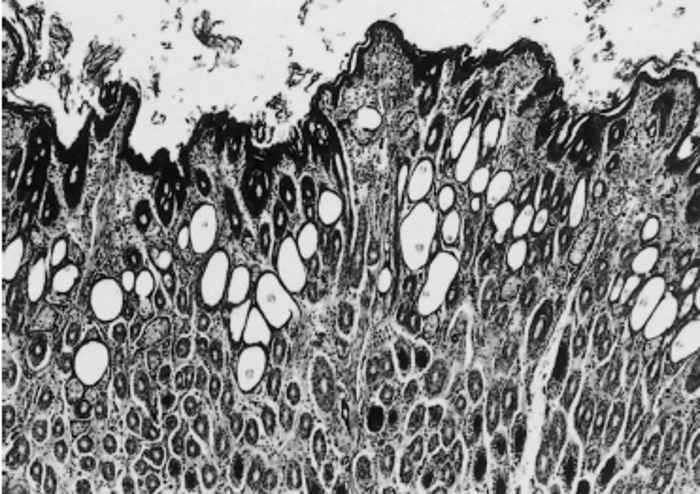

In both the early and more chronic lesions, the most consistent histopathological changes are a mild, mainly lymphocytic, dermatitis; superficial and follicular hyperkeratosis; prominent dilatation of the hair follicles (Figure 191.4); and an increase in the size and/or number of sebaceous glands. There is no exudate present on the surface of the epidermis. The sticky, scaly deposits present macroscopically are probably due to a combination of increased sebum secretion and hyperkeratotic flakes.